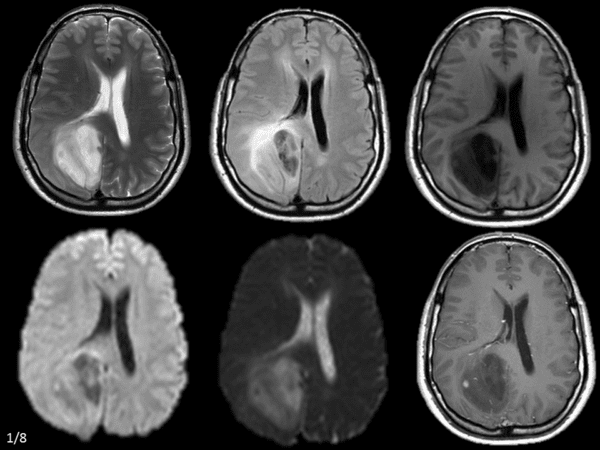

U tế bào hình sao

» Thông tin: Nam giới – 42 tuổi.

» Lâm sàng: Đau đầu.

# U sao bào kém biệt hóa (Anaplastic Astrocytoma)